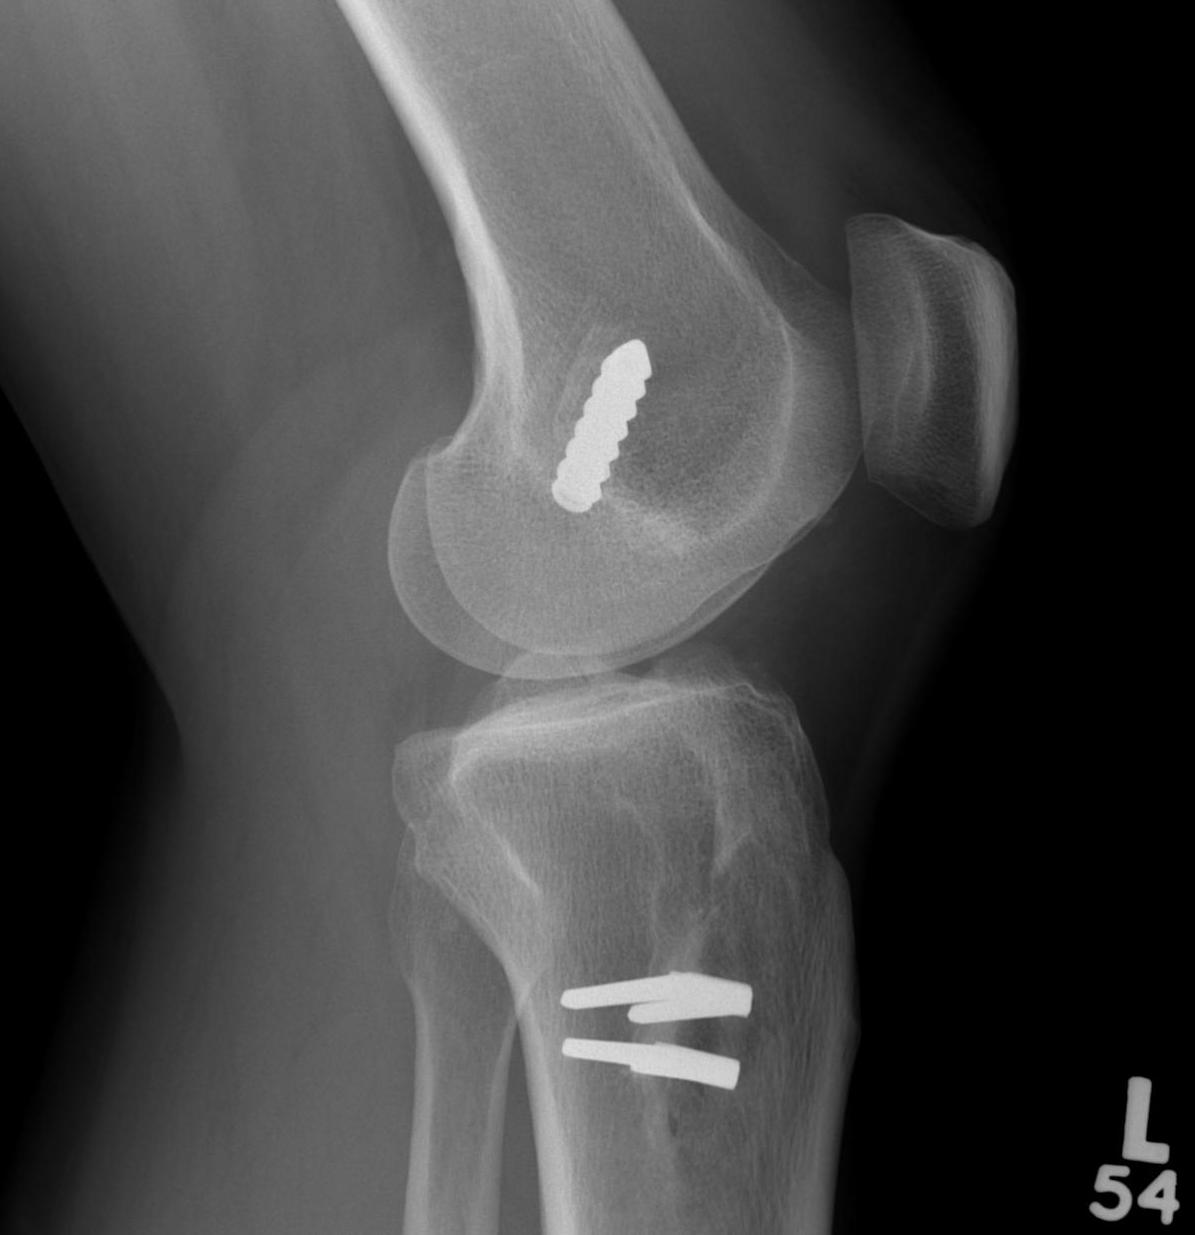

Xray

AP and Lateral

- assess tunnel placement

- Assess metal work

- types of fixation

- metal v plastic

Revision ACL Lax Graft Anterior Femoral Tunnel

Revision ACL Graft Placed posterior to old femoral tunnelRevision ACL New Posterior Femoral Tunnel